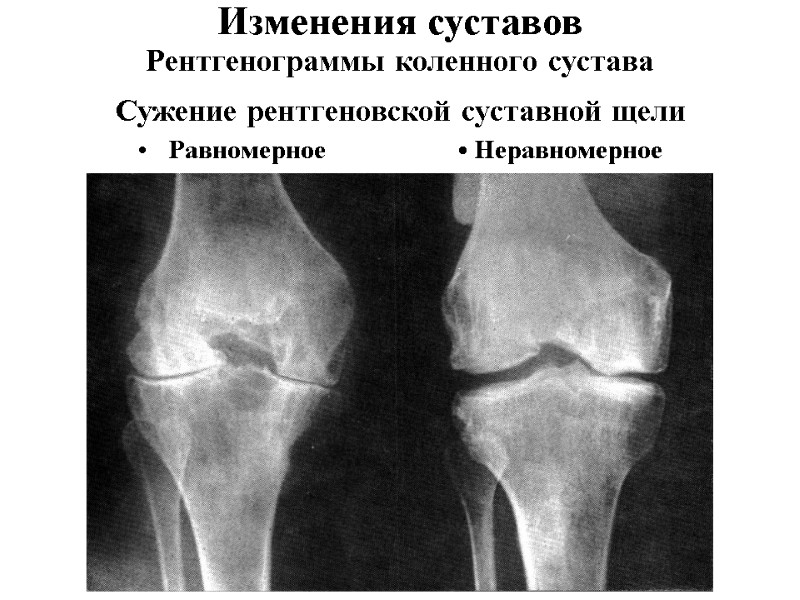

Рентгенограммы коленного сустава Сужение рентгеновской суставной щели Равномерное • Неравномерное Изменения суставов